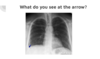

Left pneumothorax

Horizontal ribs on the right image suggesting hyperinflation

Loss of costophrenic angles and borders suggests bilateral effusion.